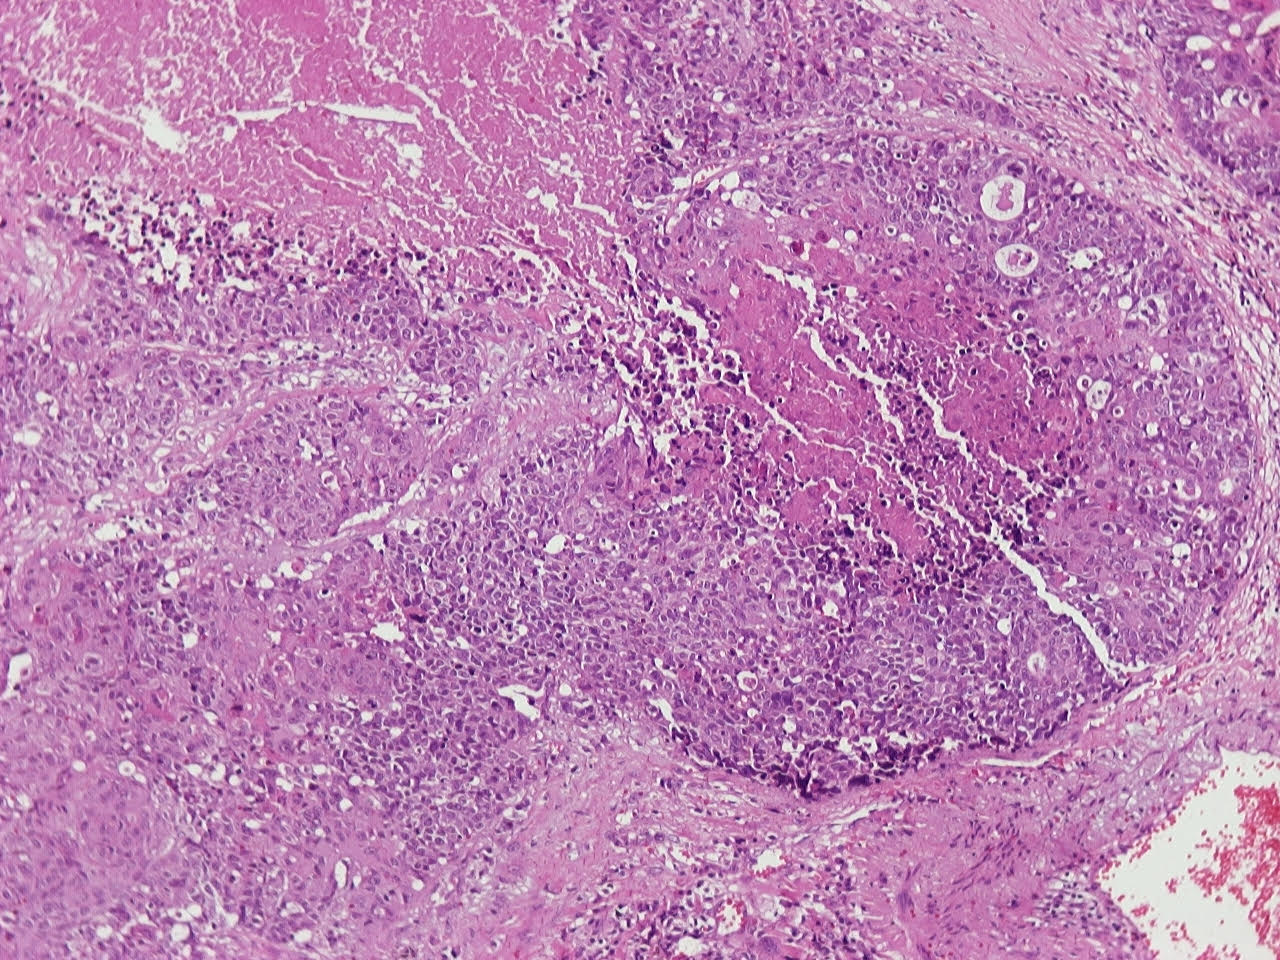

- Neuroendocrine organoid architecture may include nesting with peripheral palisading, anastomosing trabeculae and rosette-like structures (Mod Pathol 2022;35:36)

- > 10 mitoses/2 mm2, extensive / geographic necrosis

- Large cells (~3x size of small cell carcinoma) with abundant amphophilic cytoplasm, intercellular membranes, nuclear pleomorphism, variably coarse, granular or vesicular chromatin with prominent nucleoli (Transl Lung Cancer Res 2020;9:860, Mod Pathol 2022;35:36)

- Occasional rhabdoid features (Pathol Int 2019;69:481, J Cancer Res Ther 2015;11:657)

- Larger tumor cells than atypical carcinoid, high nuclear grade, increased mitotic activity and necrosis (Arch Pathol Lab Med 2010;134:1628)

Microscopic (histologic) images

Contributed by Ioanna Abba Nteka, M.D., Aggeliki Cheva, M.D., Ph.D., Antonia Loukousia, M.D., Roseann Wu, M.D., M.P.H. and Kyriakos Chatzopoulos, M.D., Ph.D.